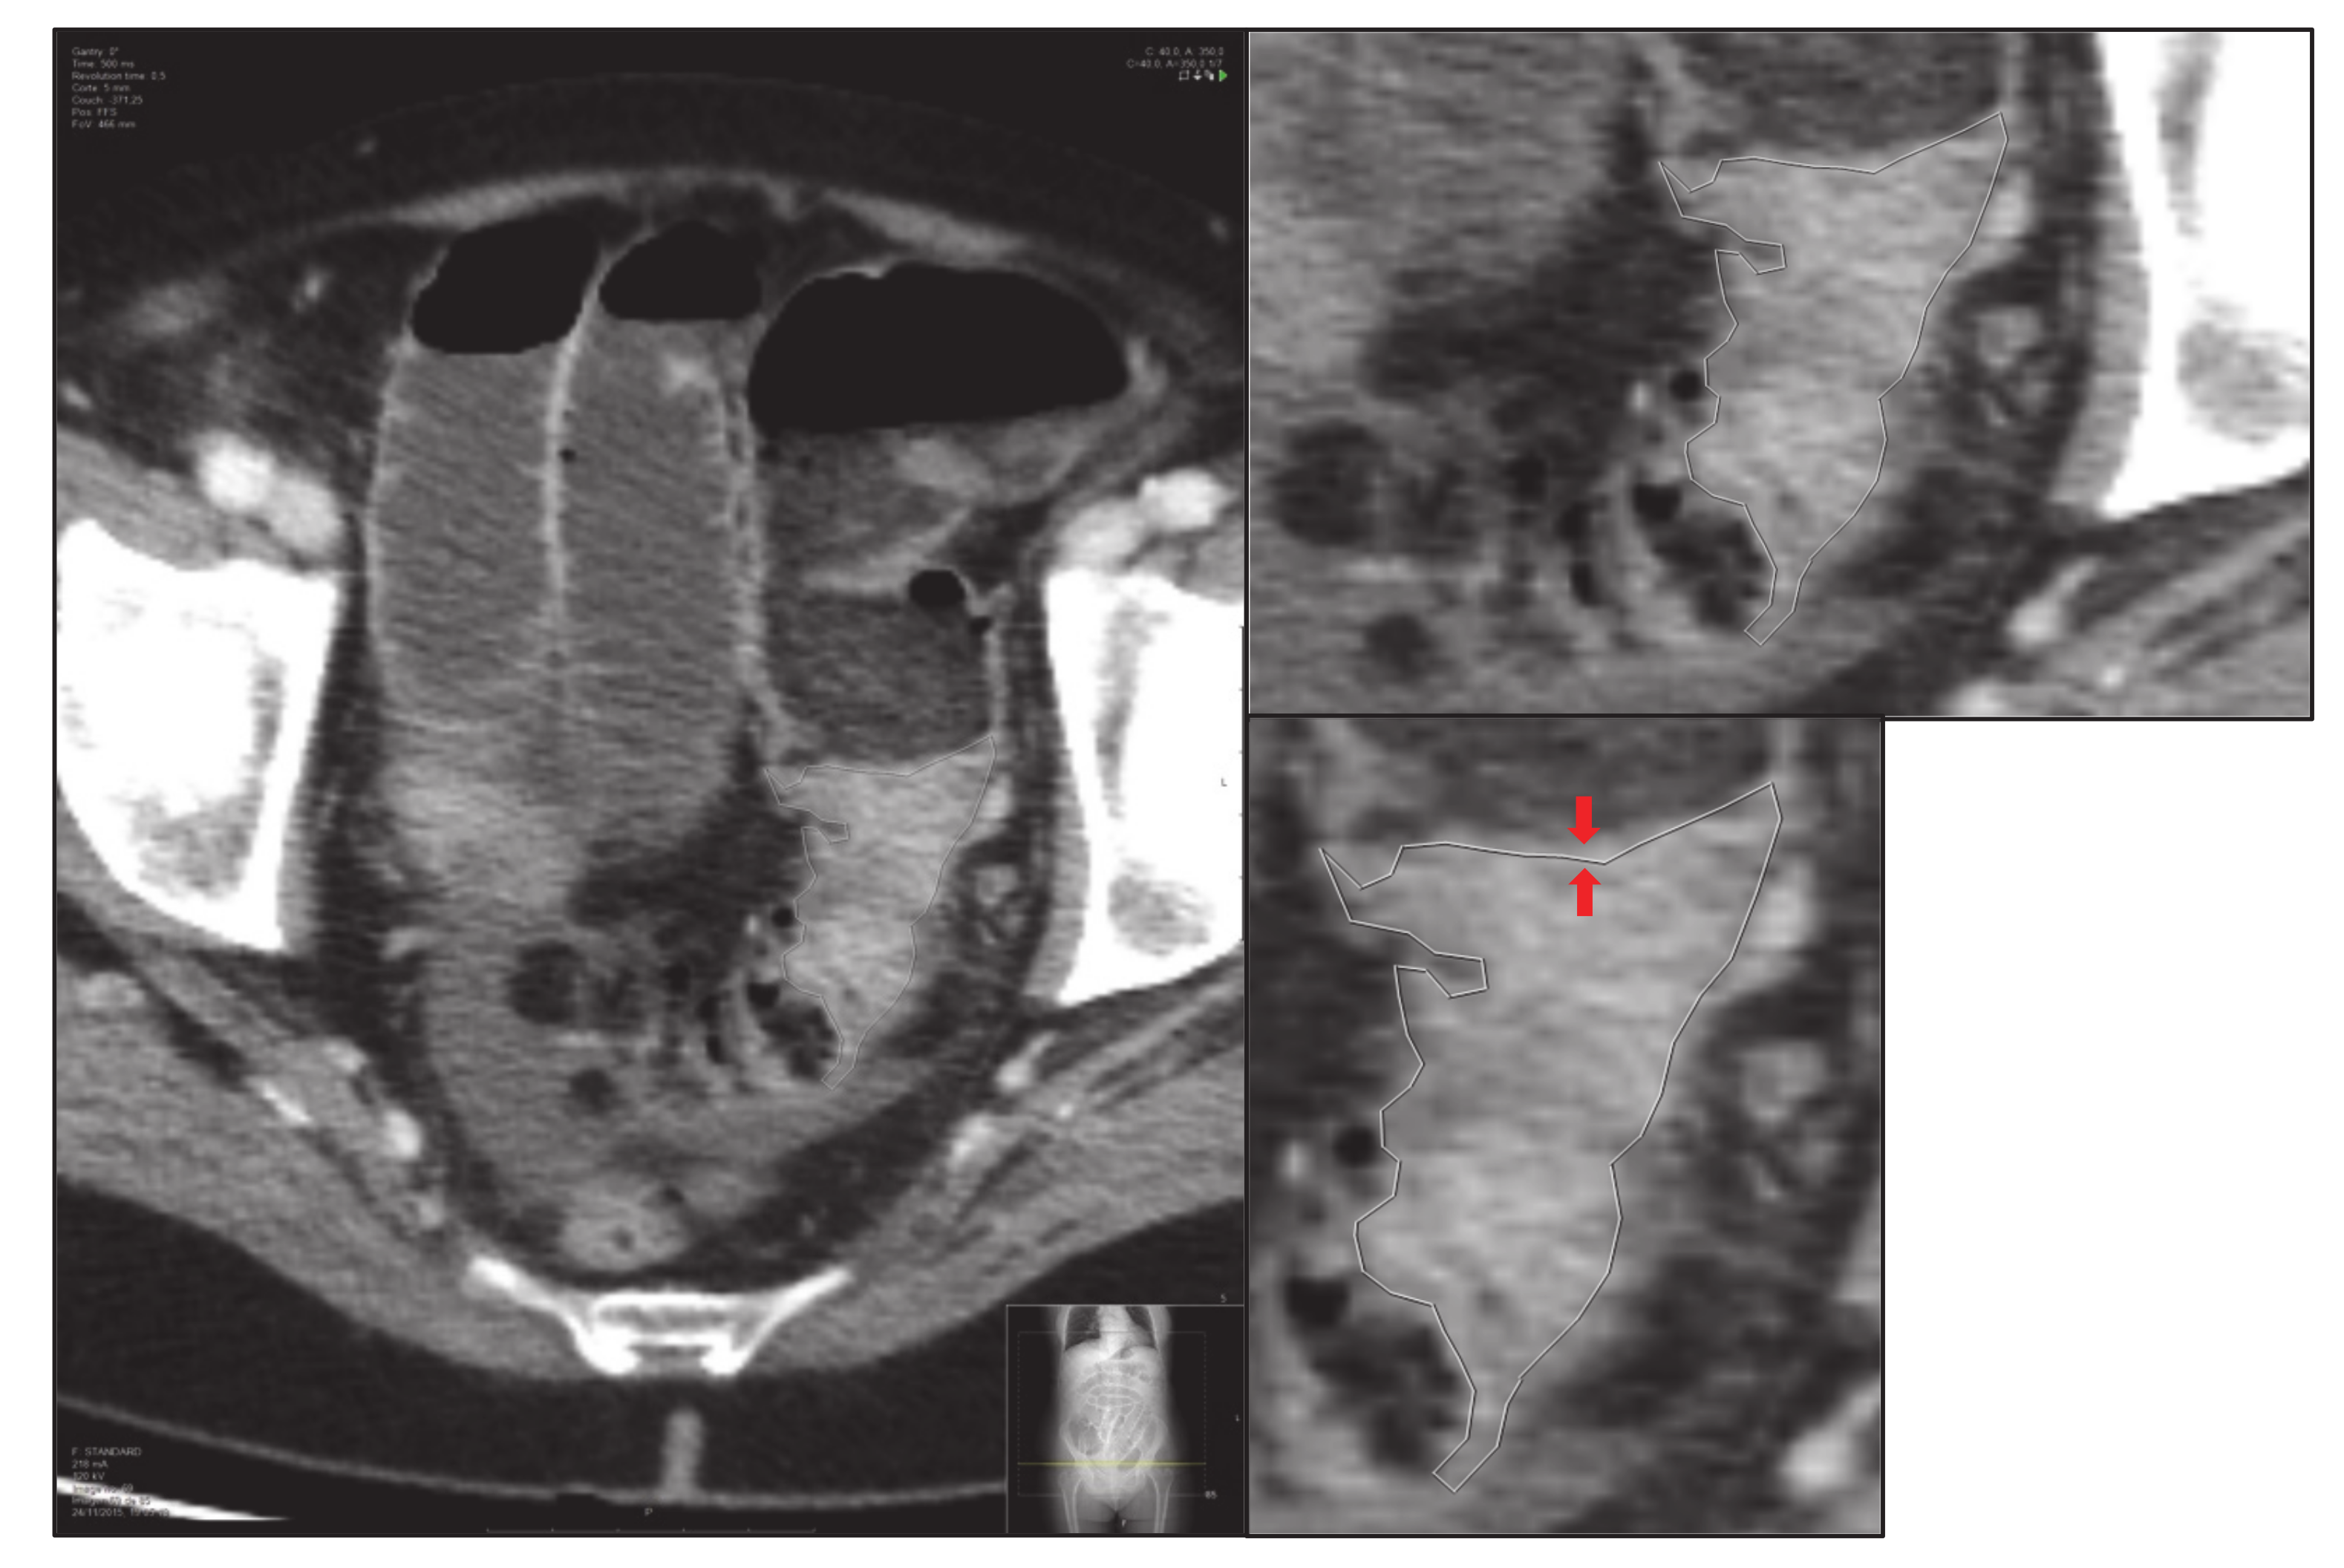

- Third, the screen zoom is adjusted by enlarging the image and an image of the segmented and enlarged tumour is saved: “small-delimited.tiff” (i.e., Figure 3).